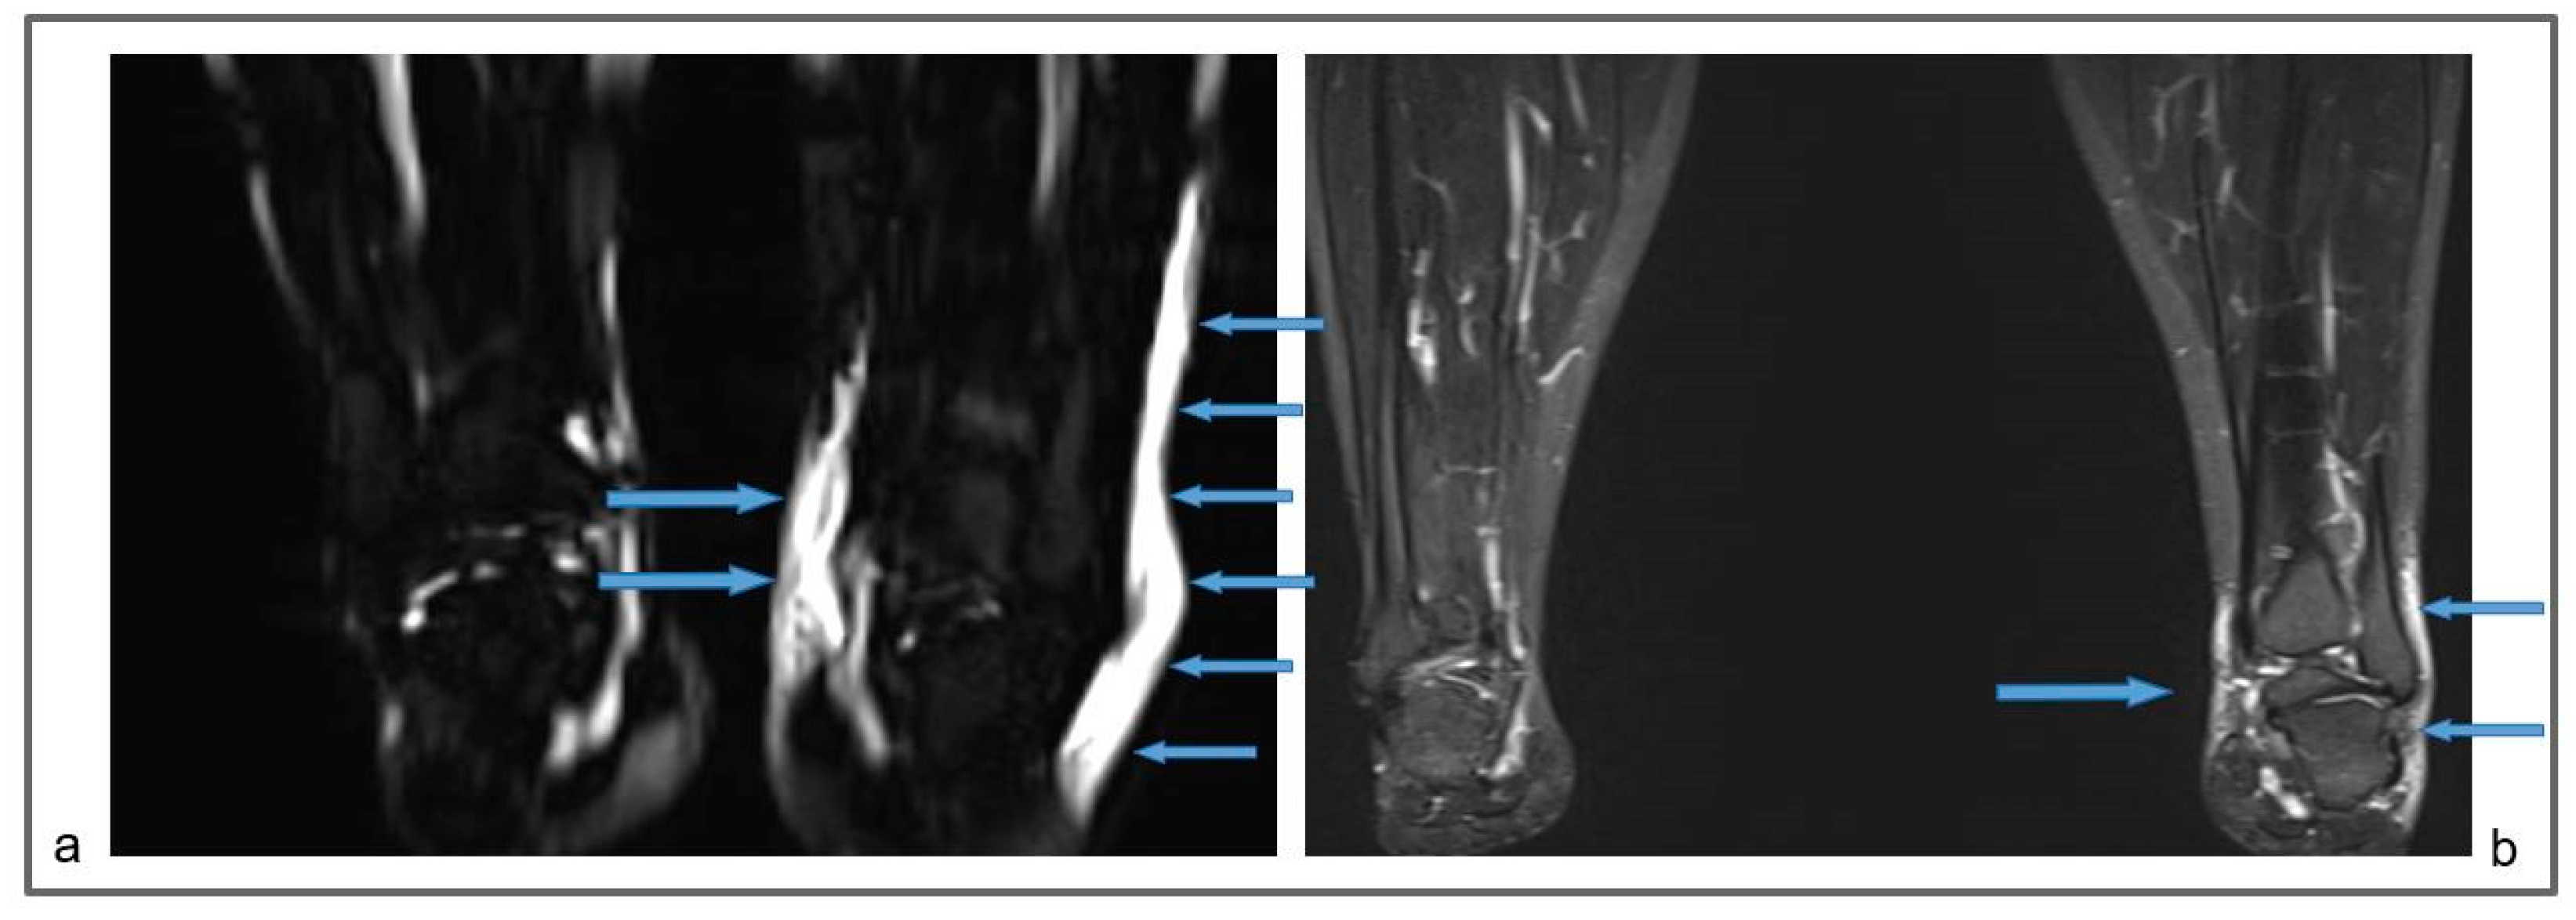

Figure 6.

Patient 3: Preoperative non-contrast MR lymphography (a) and at 1-year follow-up (b), based on high-resolution, heavily T2-weighted coronal sequences (turbo spin echo with repetition time 2870 ms, echo time 797 ms, field of view 380 × 380 mm, matrix 358 × 384, slice thickness 1 mm). The patient suffered from a marked increase in the size of the left ankle and distal leg, due to a large amount of epifascial fluid (a; blue arrows). The follow-up demonstrates a marked reduction in the epifascial fluid with a significant size reduction of the affected areas (b; blue arrows).

Figure 7.

Patient 3: Follow-up MR lymphography showing lymph nodes transplanted in the popliteal fossa (blue arrows) and coronal reconstruction of a 3D short-time inversion recovery (STIR) with repetition time 3000 ms, echo time 254 ms, inversion time 160 m, field of view 460 × 504 mm, matrix 315 × 384, slice thickness 1 mm.